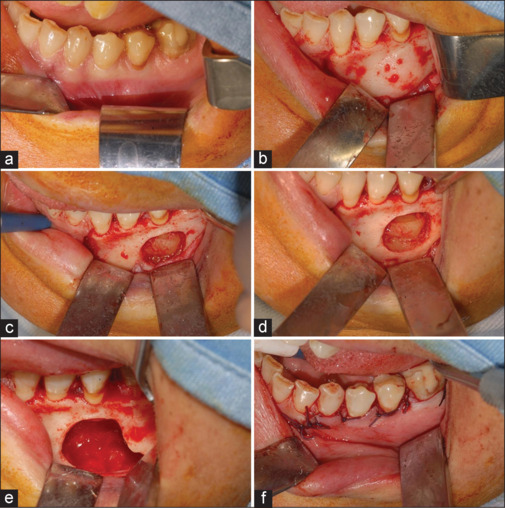

Fibrous dysplasia is a rare genetic syndrome that affects bone tissue. This pathology replaces the mineralized matrix of the bone affected with connective and fibrous tissue. This article describes a mandibular fibrous osseous dysplasia case and its surgical treatment. A 45-year-old woman complained about a slow development of swelling of the left mandibular bone. The orthopantomography (OPT) and the cone beam computed tomography (CBCT) revealed a well-circumscribed sclerotic lesion with a ground-glass appearance apical to the 3.5 element. The surgery was performed to excise the lesion. Anatomopathological examination of tissue confirmed the suspects among the diagnosis of fibrous dysplasia. The patient underwent to follow-up of 4 years, and no recurrences were found. In the absence of a univocal consensus on therapy, surgery remains the treatment of choice for unifocal forms.